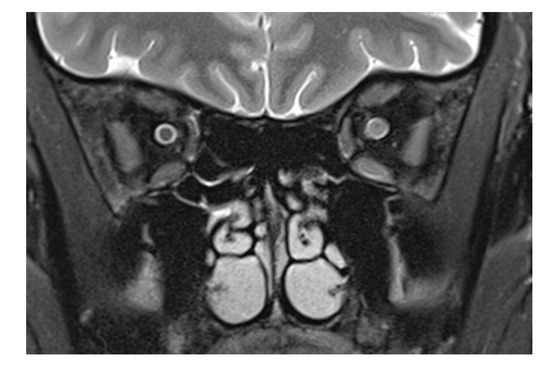

Examination of the right eye revealed a superficial conjunctival wound nasally and a dilated pupil (a). On the MRI scan, there is loss of the subarachnoid space in the right optic nerve (arrows in panel (b): the subarachnoid space of the left optic nerve is normal). The respective transverse T2-weighted image shows a central signal increase in the optic nerve (arrow in (c)). On the diffusion-weighted imaging, a punctuate signal increase in the optic nerve in the same location is seen (arrow in (d)); the corresponding ADC map shows signal loss in the same location (arrow in (e)). The globe as well as the left eye and orbit are unchanged, while there is a diffuse signal increase (arrows) in the right retrobulbar space nasally (f,g).

CT of the facial skull showed neither fractures nor foreign bodies, metallic or otherwise (Somatom Excite, Siemens Healthineers, Erlangen, Germany). The optic canal was normal. MR imaging was performed 4 hours after the trauma on a 1.5 T imager (Symphony, Siemens Healthineers, Erlangen, Germany) with a standard head coil. Plain T1w spin-echo images in the transverse orientation (TR 500 ms, TE 8.8 ms) and plain T2w turbo spin-echo transverse and coronal images with and without fat saturation (TR 4.000 ms and TE 128 ms) by prepulse were obtained in a 2 mm slice thickness. For DWI and ADC maps, a transverse orientation was chosen (5 mm slice thickness, TR 2500, TE 80 ms, and b-value of 1.000 s/mm2). Imaging demonstrated on coronary T2-weighted fat-saturated MRI loss of the subarachnoid space in the right optic nerve (white arrows in panel b: the subarachnoid space of the left optic nerve is normal) while the respective transverse T2-weighted image revealed slight optic nerve distention with a central signal increase (white arrow in c) right frontally from the optic canal. Diffusion-weighted imaging showed a punctuate signal increase in the optic nerve in the same location (d); the corresponding ADC map had signal loss in the same location (e). The globe was unchanged, while the retrobulbar space showed a diffuse signal increase nasally (f,g). The left eye and orbit were normal.

The patient presented here had direct trauma to the right eye, and MRI was performed after full ophthalmological examination, only hours after the trauma in a conscious and cooperative patient. The trauma was a “perforating stab wound” [4] but missing the globe. The only sequela clinically visible was a conjunctival tear. CT excluded soft tissue changes, fracture, and foreign bodies in the globe and orbit. On MRI, changes in the optic nerve (and impossible to be seen on CT) were noted. This structure showed an opacification of the subarachnoid space, compatible with hemorrhage: an increase in the T2 signal of the optic nerve anterior to the inner opening of the optic canal; an increase in signal intensity on the diffusion-weighted b1000 image; and a decreased signal in the ADC map in the same location. The obliteration of the subarachnoid space around the optic nerve was different from what is commonly seen in the enlargement of an optic nerve. (For comparison, Figure 2 shows a T2-weighted image of an inflamed optic nerve in a patient with multiple sclerosis. There, the nerve supplants the subarachnoid space, which in comparison to the right and unaffected side is less wide).

T2-weighted frontal image in a multiple sclerosis patient with optic neuritis. While the subarachnoid space has a normal diameter on the left, an enlarged optic nerve encroaches in the same space, recognizable by the smaller liquor-filled rim of the nerve. Leakage of cerebrospinal liquor after direct laceration of the sheath, however, cannot be counted out. The diffuse signal increase of the nasal retrobulbar space in Figure 1f,g may be explained by cerebrospinal liquor leaking from an injured optic nerve sheath and by edema.